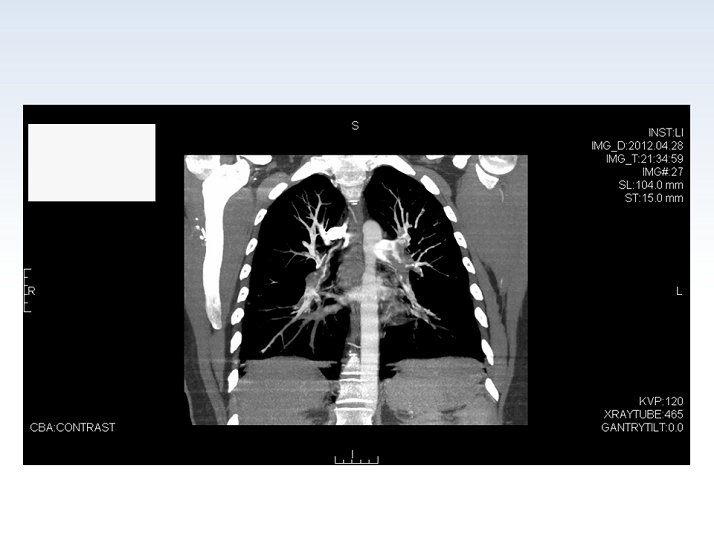

- Figure 15

CT Scan